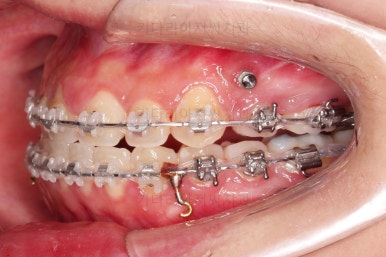

부산치아교정 이번 치료의 핵심인데요.

결손 부위에 미니스크류를 이용해서 뒤쪽 어금니들을 결손 부위로 앞으로 앞으로 계속 당겨줍니다.

얼굴모습에서의 중앙선도 지속저으로 체크하면서 한 쪽으로 치우침 없이 마무리를 해야 하고요.

틈새가 줄어들 때 까지 같은 작업을 반복합니다.

점점 틈새가 붙어가는게 보이죠?

계속 반복합니다.